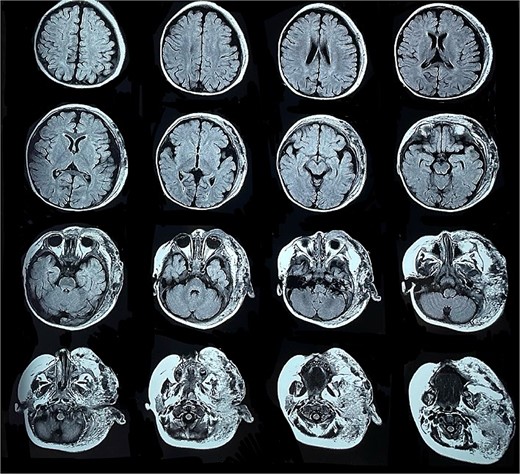

Six months later, the patient developed fever and severe edema that prevented the opening of the left eye, resulting in decreased overall tolerance. Laboratory results showed leukocytosis, severe thrombocytopenia (platelet count of 6000), and a positive C-reactive protein test. Physical examination revealed an irritable and lethargic patient with a 15 × 20 cm red mass with irregular borders (Fig. 1). An angioresonance was performed, revealing a hemangioma on the left hemiface that infiltrates muscle planes, the left parotid gland, and the auricular pavilion, ~10.7 × 6.6 × 13 cm in size, with possible vascularization from branches of the external carotid artery (Figs 2 and 3), leading to the diagnosis of KMP.

Angioresonance with evidence of a hemangioma on left hemiphase (cross-sectional).